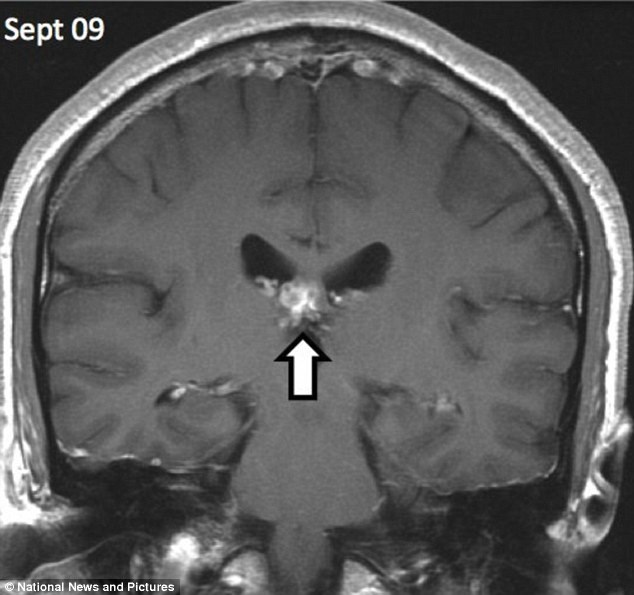

Hình chụp não bệnh nhân bị sán dây xâm nhập (ngày 9/9)